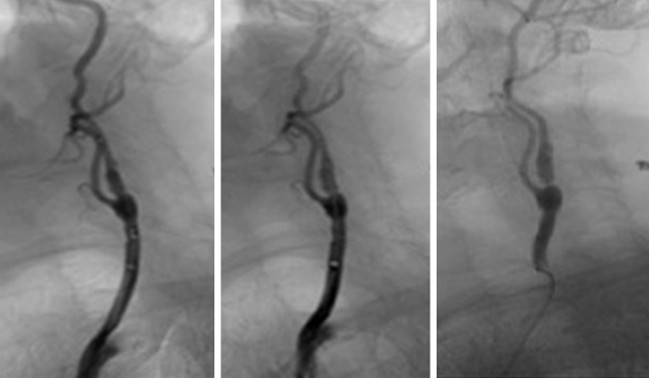

(3)頸椎內外血管扭曲:

抬頭、擺動頭頸部或長期姿勢不良等,導致頸椎內外血管流動不暢順,影響血液來往腦區域,導致頭暈、頭痛。

目前,採用強力後枕牽引器(N05b) 拉直頸椎,減少病變對神經的受壓,減少刺激交感神經,同時可拉直血管,使血液流通暢順。此方法可從根源解決頸源性頭暈、頭痛、眼花等問題,非常有效。

先讓病人頭部保持後仰姿勢,並以後枕作為支點,再扭動兩側升降桿的扭制,產生巨大後枕牽引力(最高可達到20Kg)有效拉直上頸部,減少刺激交感神經,減少頸椎神經受壓和暢順頸部血管。